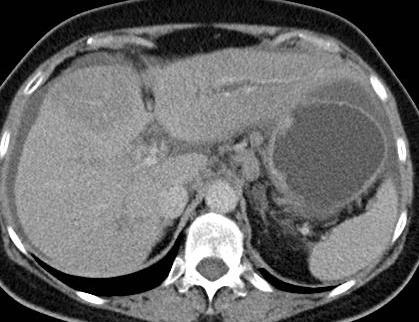

Portal Venous Occlusion

Needs adequate portal vein supply